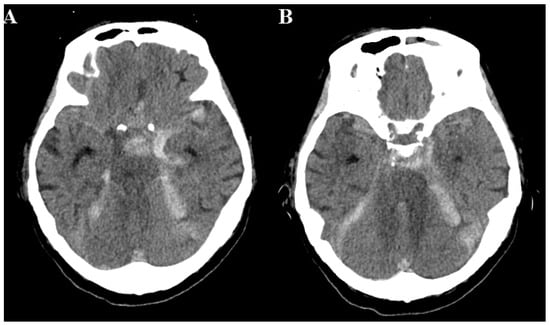

2. Case Presentation